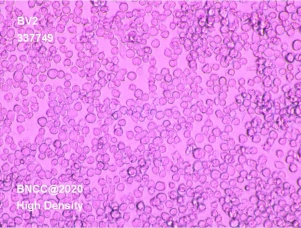

小鼠小胶质细胞